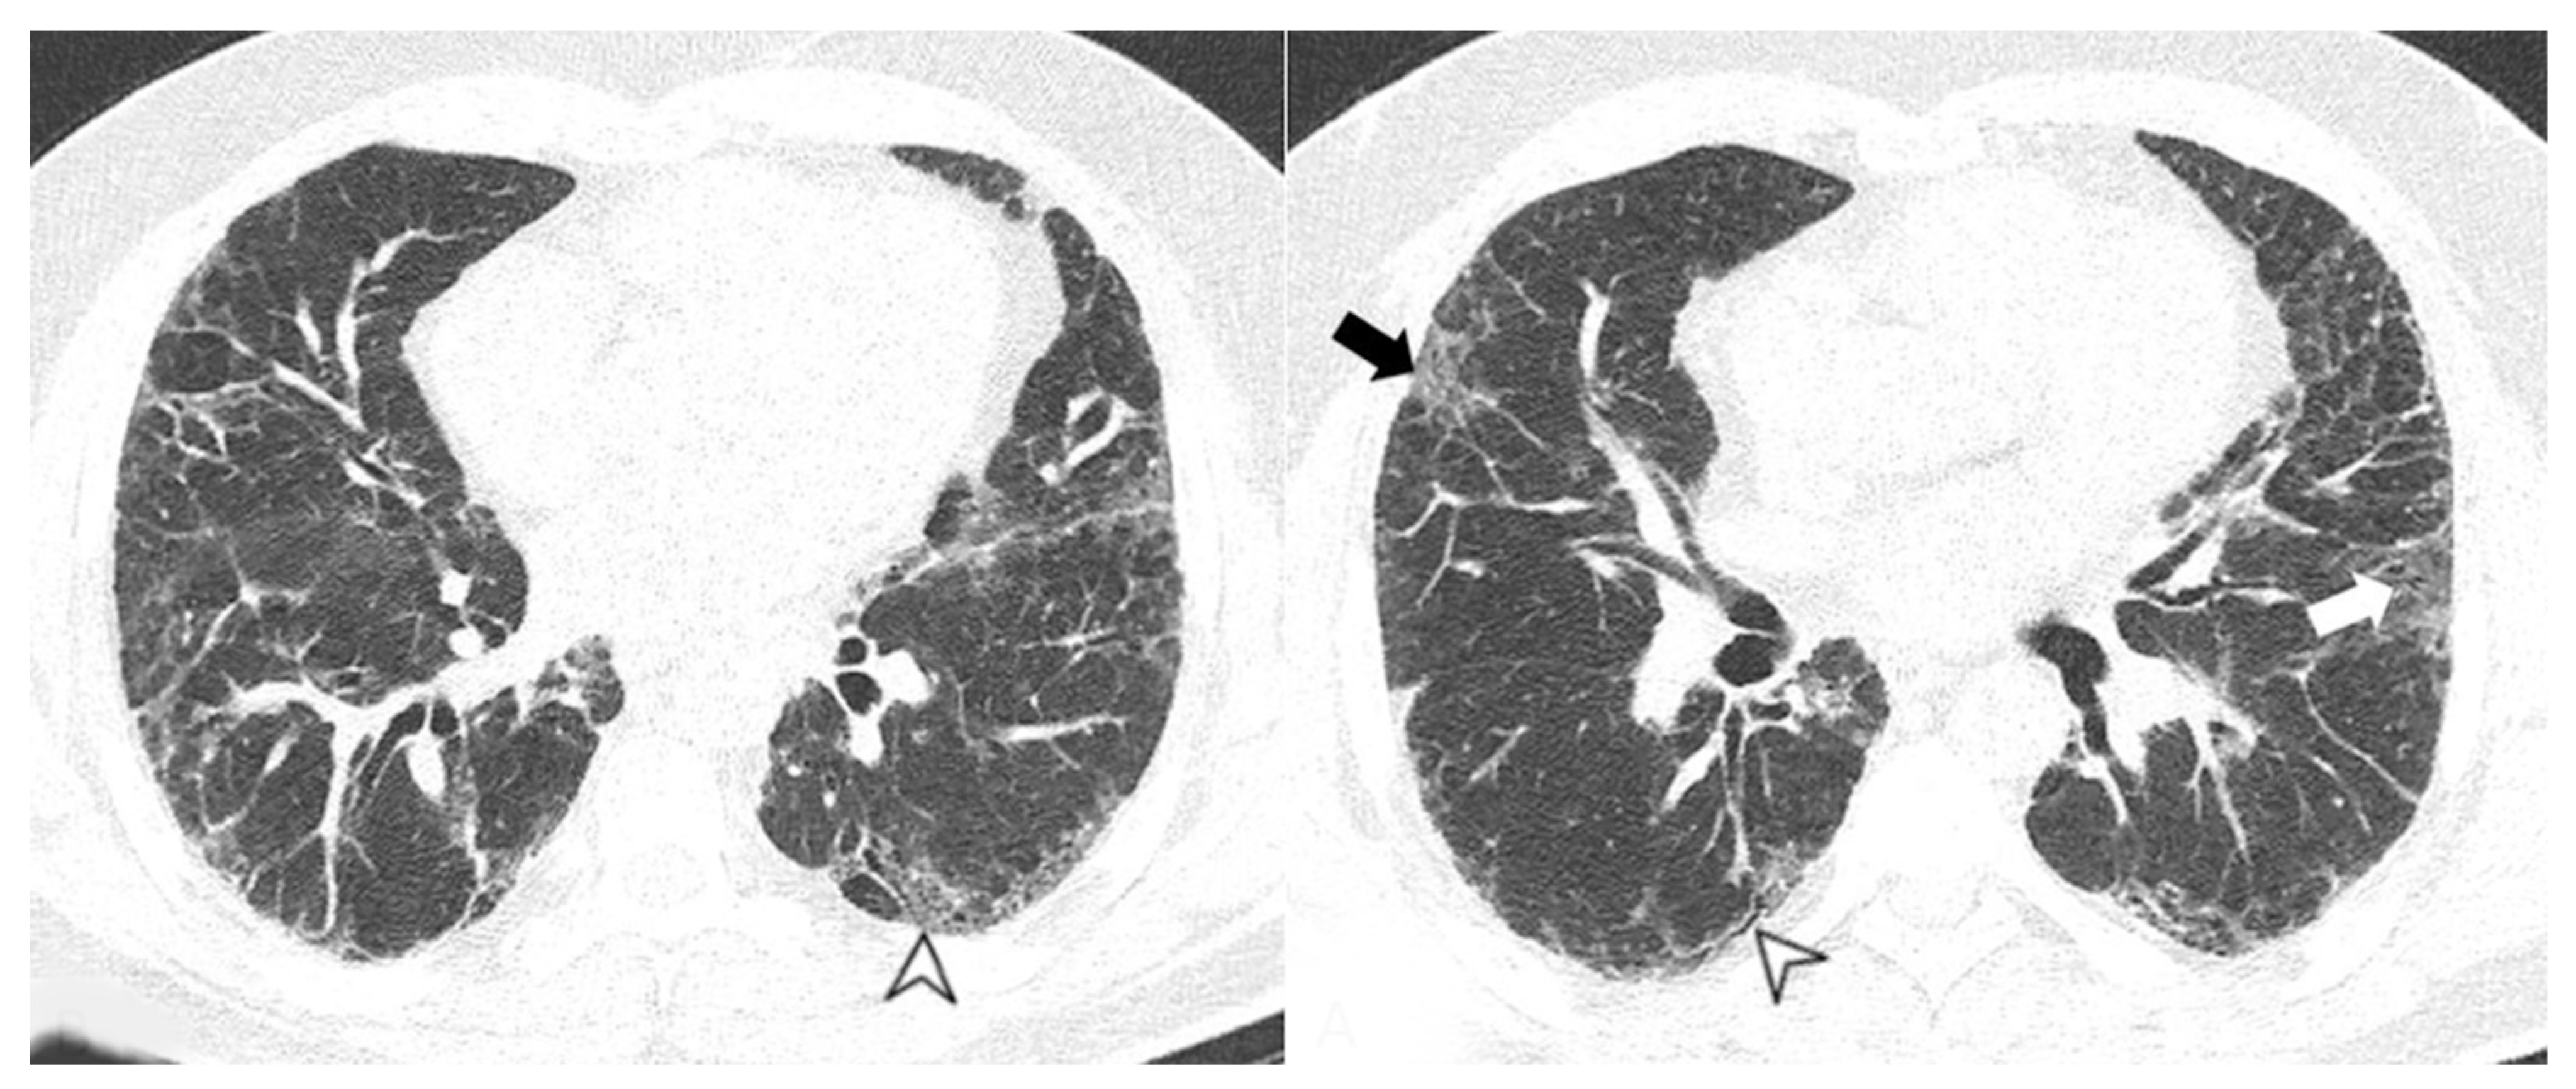

4.2.1. HRCT Findings of Patients with Anti-ARS Abs

4.2.2. HRCT Findings of Patients with Anti-MDA-5 Abs

| Lesions | GGO, reticulations, consolidations | consolidations, GGOs | |

| Distribution | Homogeneous; lower lung lobes, along bronchovascular bundles and lung periphery; loss of volume of lower lobes | Patchy; peripheral lower lobes or along the bronchovascular bundles | |

| CT pattern | NSIP OP NSIP-OP UIP DAD-unclassifiable | 50% 20% 25% 10% +/− | 20% 50% 25% <5% ++ |